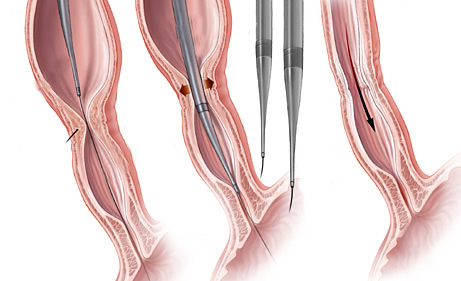

- Dilatadores flexíveis: uma série de sondas graduadas (espessura crescente) chamadas de sondas termoplásticas podem ser usadas. Estes são tubos que passam através do esófago para o estômago. Os tubos utilizados tornam-se progressivamente maior, até que o tamanho desejado seja atingido

- Balões dilatadores: a dilatação do esôfago pode ser feita usando balões durante a endoscopia. A endoscopia flexível permite ao examinador visualizar diretamente a estenose. Um balão é introduzido pelo canal do aparelho até a zona de estreitamento. Ele é então insuflado com água até uma certa pressão, que é pré-ajustada para uma dada circunferência. Quando insuflado, torna-se em forma de salsicha, esticado, e faz com que a estenose se abra.

Tratamento da Acalasia

- A Acalasia requer um tipo de balão específico, mais longo e maior, chamado de balão pneumático. Nesta situação, as fibras musculares espásticas na parte inferior do esôfago são esticadas.

Estenoplastia

Em algumas ocasiões, o estreitamento (estenose) é tão grande que nem os instrumentos de dilatação conseguem passar. Nestes casos e em algumas outras situações, realiza-se o procedimento de estenoplastia. Este consiste na realização de pequenos cortes na região da estenose com auxílio de um estilete que é passado pelo canal de trabalho do endoscópio. Estes pequenos cortes ajudam abrir o estreitamento facilitando a passagem dos dilatadores e acelerando o processo do tratamento. Em alguns casos após a realização dos pequenos cortes algumas substâncias, como corticóides, são injetadas na região para prevenir que o estreitamento feche novamente com facilidade.